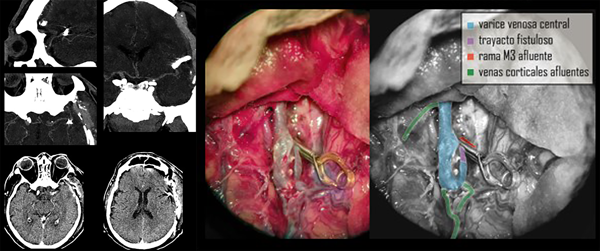

Cuidados neurocríticos postoperatorios

En forma inmediata se tomaron medidas de control de la presión arterial para disminuir los riesgos de sangrado. Al cabo de 24 horas se reinició también la terapia antitrombótica. A las 48h de registro de presión intracraneal normal y sin cambios significativos en el examen físico (paciente sedado en ARM) se realiza imagen de control (TC y AngioTC) en la cual puede observarse ausencia de nuevas lesiones hipodensas, presencia de clip vascular en cisura silviana, permeabilidad de vasos silvianos distales al clipado, disminución significativa del volumen original de la várice venosa, desaparición del higroma contralateral, surcos y cisuras presentes en el hemisferio derecho y ligero edema regional fronto temporal izquierdo (Figura 4).

Figura 4. TC y AngioTC de control postoperatorio y fotografía quirúrgica esquematizada.

Con la premisa de actuar en forma urgente para evitar resangrado y luego de superado un evento infeccioso de origen respiratorio, se decide realizar una nueva cirugía a los 5 días de su ingreso con el objetivo de tratar la lesión vascular de alto flujo. En quirófano se pudieron constatar con precisión los datos obtenidos por imágenes de la angioarquitectura patológica. Se inició por la disección microscópica del valle silviano, exposición de los vasos comprometidos y control proximal vascular de la malformación. Se identificó un trayecto fistuloso de entre 5 y 7 mm de largo que provenía de una rama M3 que drenaba en el trayecto varicoso central. Se realizó clipado transitorio en la base de este trayecto y coagulación de 2 pequeñas aferencias fistulosas a la várice.

Luego de comprobar disminución notable del flujo y el volumen de la várice venosa, se colocó clip definitivo. La várice venosa en su tramo distal presentaba afluentes venosos de caracteres normales que provenían de la corteza, por lo cual no se realizó ningún otro gesto sobre la misma. Se realizó cierre por planos y craneoplastia con polimetil-meta-acrilato (PMMA). Se dejó un catéter subdural para control de la presión intracraneana.